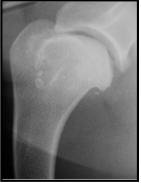

What is wrong here with this radiograph?

Mineralisation of soft tissues

Supraspinatous muscle

Bicipital groove